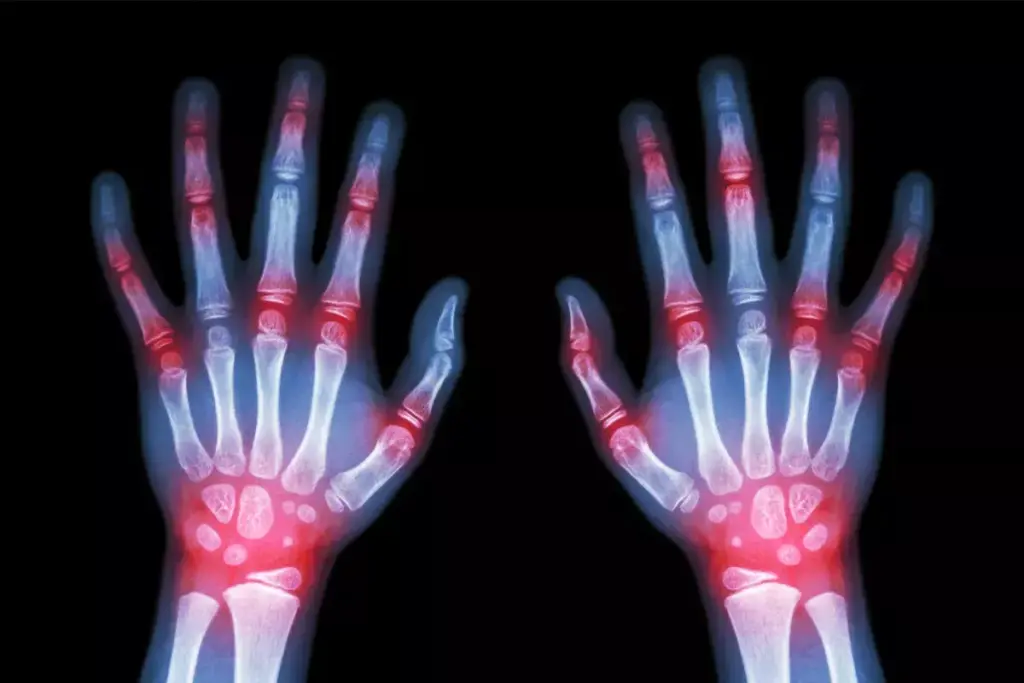

Rheumatoid nodules are firm, non-tender lumps under the skin. They can be small or quite large. They often appear on the hands, feet, and elbows.

Common Locations on the Body

Rheumatoid nodules usually pop up over joints that get a lot of pressure or trauma. You often find them on the fingers, elbows, and the backs of the heels.